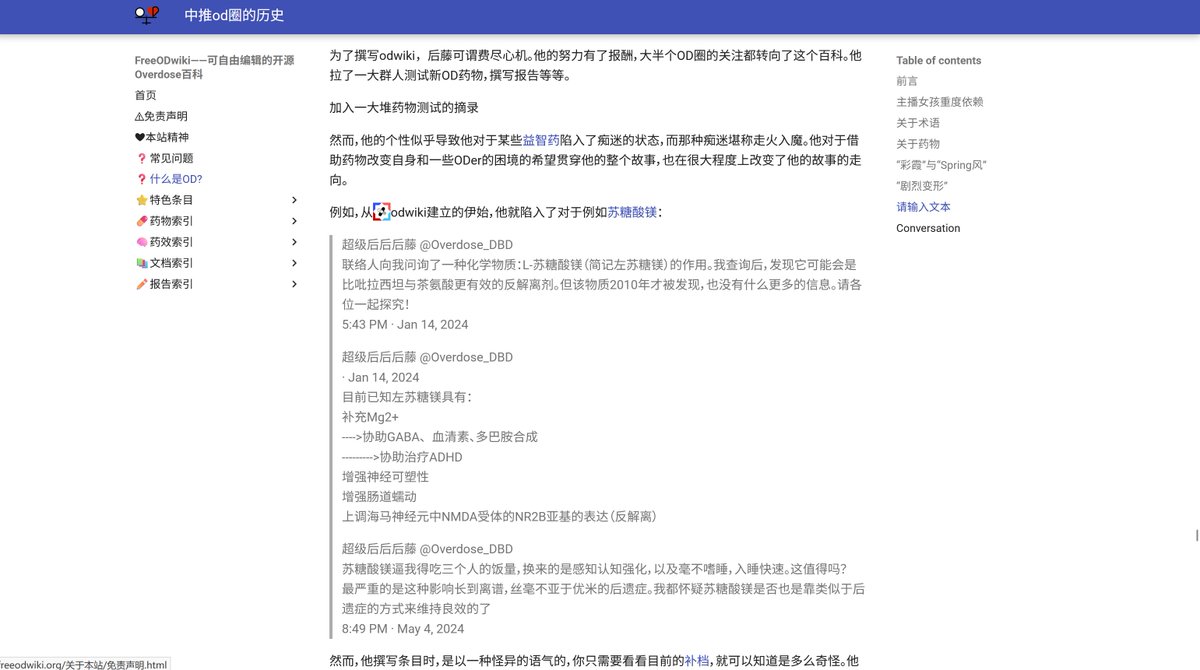

关于后藤提到过的“反解离”

首先,从定义上讲,“反解离(anti-dissociative)”并不是一个标准的医学术语或者广泛认同的药理学分类。在正规资料,比如医学文献、维基百科、精神药理学教科书中,目前并没有“反解离药物”这个正式概念。

看上去像是为了描述某类特定效应而创造的术语(可能是nmda受体活性增强),用来对抗因NMDA受体拮抗剂(比如氯胺酮、DXM、PCP等)引发的解离体验(dissociation)。

那么更常见的是将其归入认知增强剂(cognitive enhancers),特别是改善认知连接性(connectivity)和现实感知(reality testing)的类型。

但其实在药理学上,单纯用“受体激动剂”来逆转“受体拮抗剂”的效应,有时会导致过度激活。

对于NMDA受体而言,过强的NMDA活化本身就与兴奋性毒性(excitotoxicity)和精神病样症状(psychotomimetic effects)有关,比如谷氨酸风暴可以引发严重的焦虑、妄想、乃至癫痫。

也就是说,简单地“激动-解除拮抗”在中枢神经系统是很危险的做法,尤其是对于易感个体(如有精神分裂素质的人)。

科学的处理方式一般是通过更细致的调节,比如微调NMDA/AMPA平衡、调节其他辅助途径(如GABA、5-HT、mGluR受体),而不是简单粗暴地用“NMDA增强剂”去顶回去。

而临床处理药物中毒中,其实医生更常用的做法是保守、支持性的治疗,比如补液,促进代谢,必要时镇静,以及监测生命体征防治并发症。